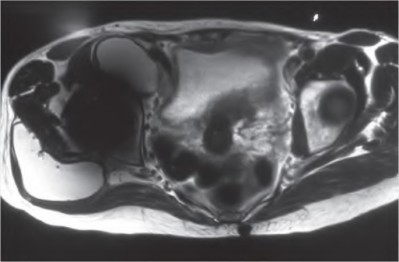

A 62-year-old male presents with groin pain and a palpable mass 5 years after receiving a metal-on-polyethylene total hip arthroplasty with a large diameter modular cobalt-chromium head on a titanium stem. Serum cobalt levels are significantly elevated while chromium levels are mildly elevated. A metal artifact reduction sequence (MARS) MRI shows a cystic pseudotumor. What is the most likely diagnosis?

Explanation

Question 21

A 60-year-old male presents with groin pain 8 years after a metal-on-metal total hip arthroplasty. Lab results show elevated serum cobalt and chromium levels. MRI with MARS (Metal Artifact Reduction Sequence) shows a solid and cystic mass communicating with the joint space. What is the characteristic histological finding in the periprosthetic tissue of this condition?